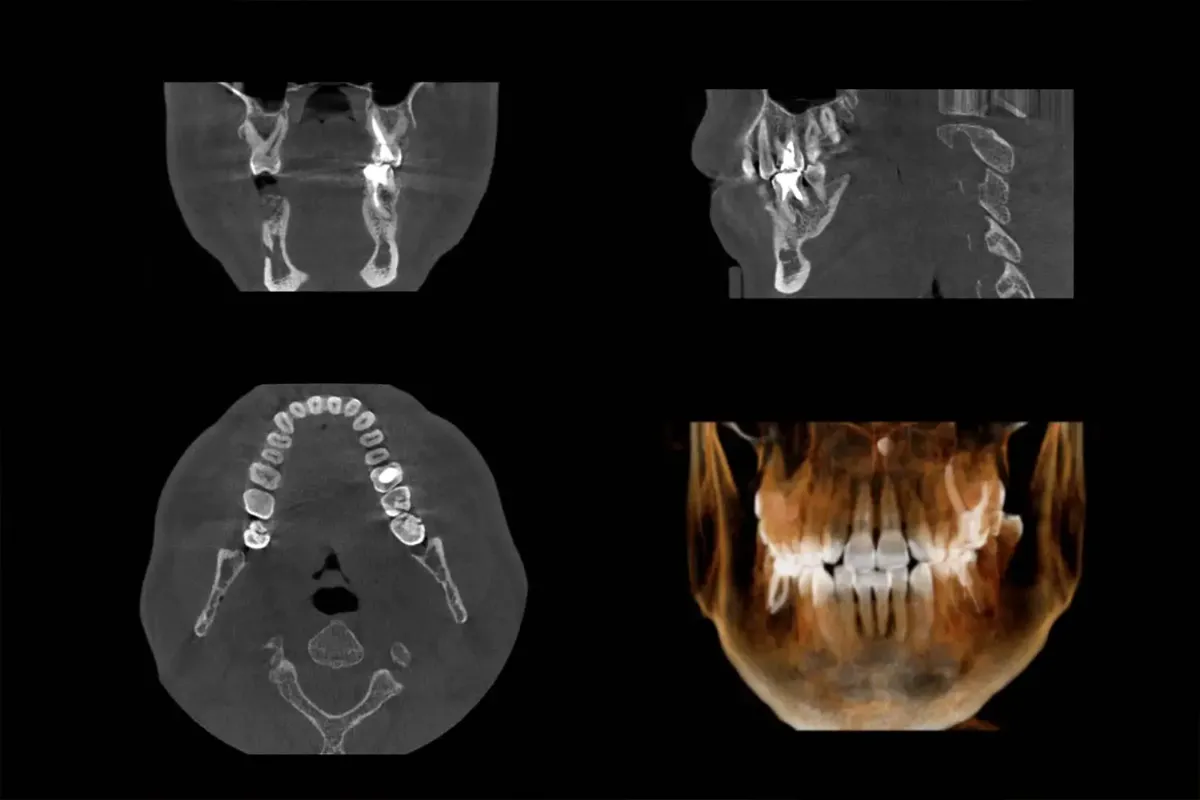

Voor complexe pijnklachten en implantaten kunnen we nu ook tandheelkundige CT-scans maken

Middels Guided-Implantology wordt implanteren voorspelbaar toevoegen van extra tanden en kiezen.